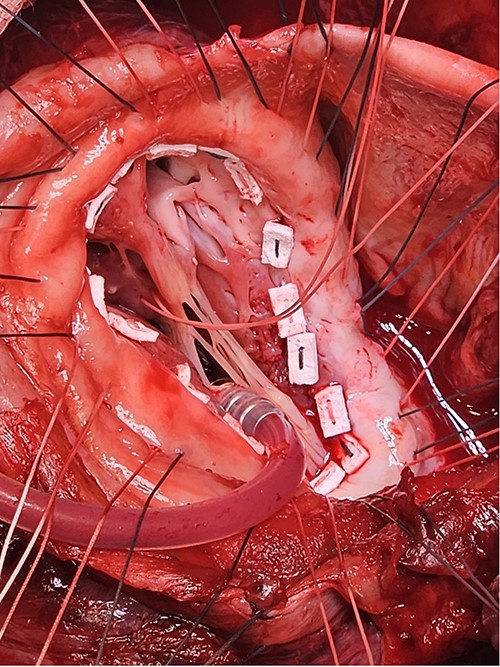

Following median sternotomy, cardiopulmonary bypass was instituted (bicaval drainage, ascending aortic return). Antegrade cardioplegia was delivered with aortic root venting and bicaval snaring. Dense adhesions surrounded the aneurysm, which had a thin wall, measured ⁓15 cm from LV apex to mitral annulus, and contained around 150 g of clot. The posterior mitral leaflet appeared retracted, preventing coaptation due to LV stretching. The aneurysm was resected (Fig. 2), and the LV wall repaired with a 5 × 3 cm patch, restoring normal LV size (Fig. 3). The musculotendinous junctions of the anterior and posterior papillary muscles were approximated using pledgeted 3–0 polypropylene sutures (Fig. 4). The patch repair was completed (Fig. 5), and the overlying sac oversewn for haemostasis.

Once the sutures for the patch were placed, the two papillary muscles were identified and another pledgeted suture through the musculotendinous junction was used to approximate them.